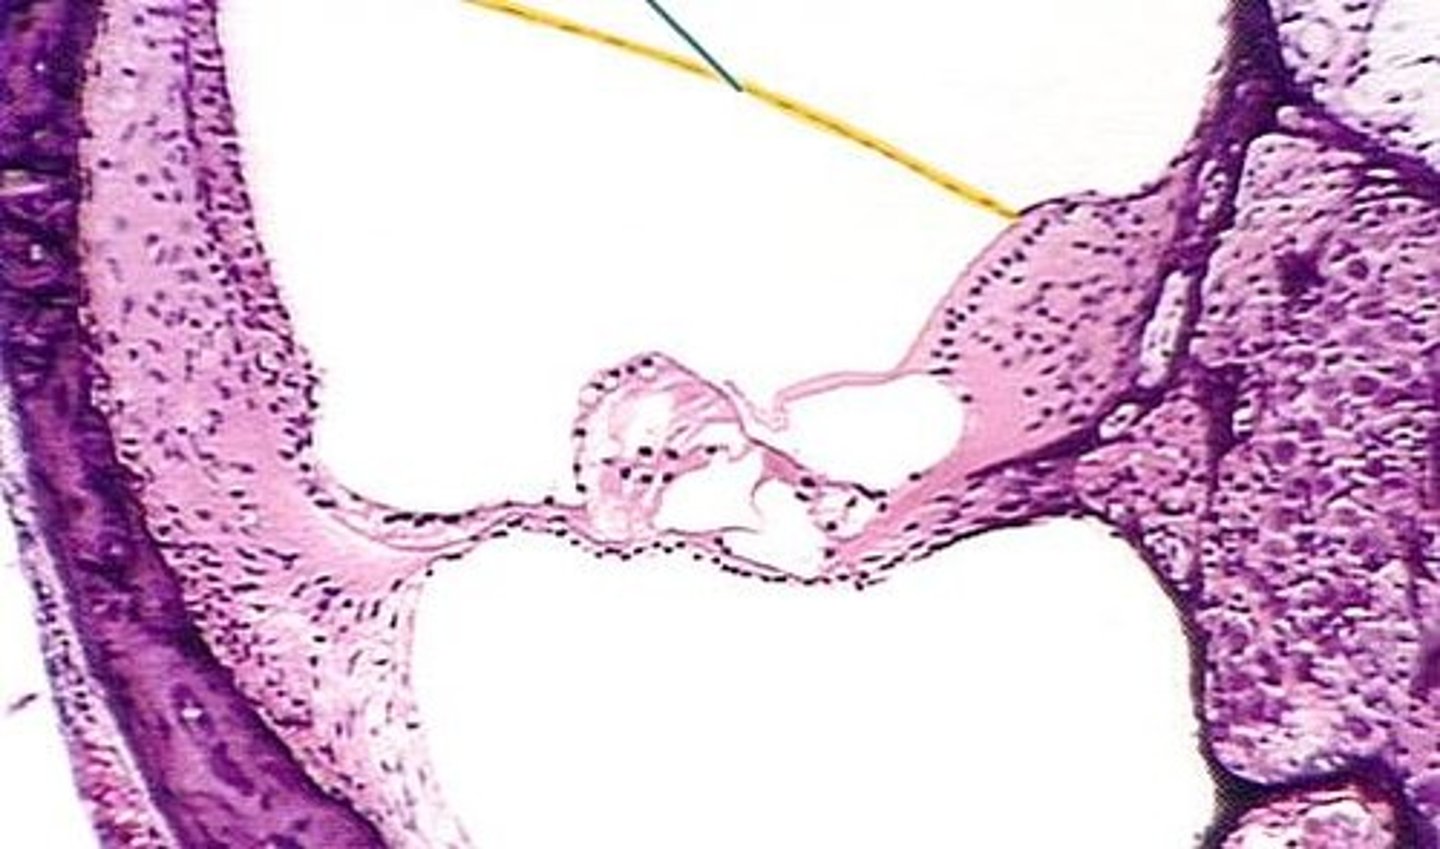

vestibular membrane

Name the yellow line

tectorial membrane

basilar membrane

organ of corti